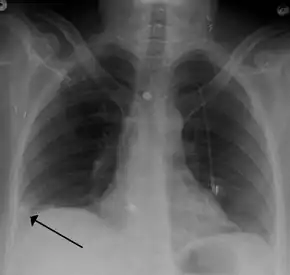

A Hampton hump in a person with a right lower lobe pulmonary embolism

• Chest X-rays are often done on people with shortness of breath to help rule-out other causes, such as congestive heart failure and rib fracture. Chest X-rays in PE are rarely normal,[60] but usually lack signs that suggest the diagnosis of PE (for example, Westermark sign, Hampton's hump).